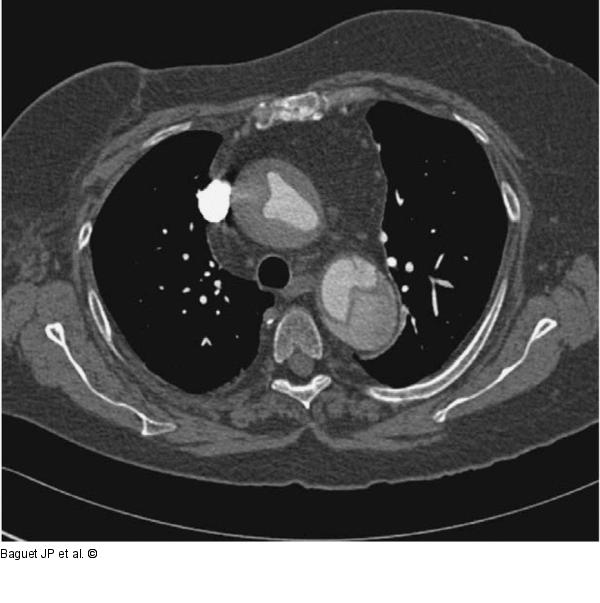

Abbildung 2: Aortendissektion

CT-Scan mit Kontrastmittelinjektion: Aortendissektion Typ A. |